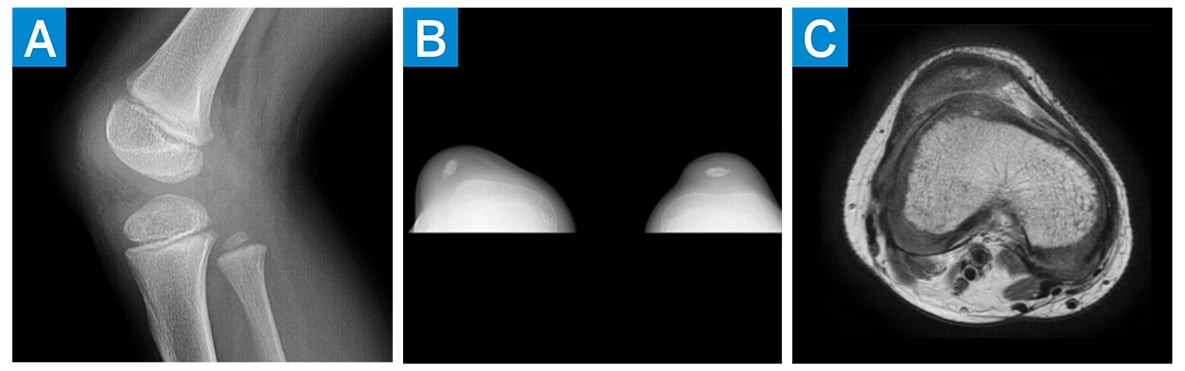

An 8-year-old boy presented with recurrent pain and patellar instability of the right knee with increasing difficulty walking and running. Physical examination showed knee range of motion of 0–120° and genu valgum in the right knee worse than the left. Additionally, there was an obligatory lateral dislocation of the patella in knee flexion with spontaneous reduction in extension. The patient had patellar apprehension and was not able to actively extend his right knee from a flexed position. Of note, he had a Beighton score of 4/9, and both his mother and brother had undergone surgery for patellar instability. Radiographs showed mild lateral subluxation of the right patella and a small primary ossific nucleus, consistent with immaturity (Fig. 1).

Figure 1: (a) Preoperative lateral X-ray of the patient’s right knee, (b) preoperative merchant view of the knees, and (c) preoperative axial MRI of the right knee.

Magnetic resonance imaging (MRI) demonstrated lateral subluxation of the patella, trochlear dysplasia, and intact articular cartilage (Fig. 1). Surgery was recommended, and the patient underwent the following: